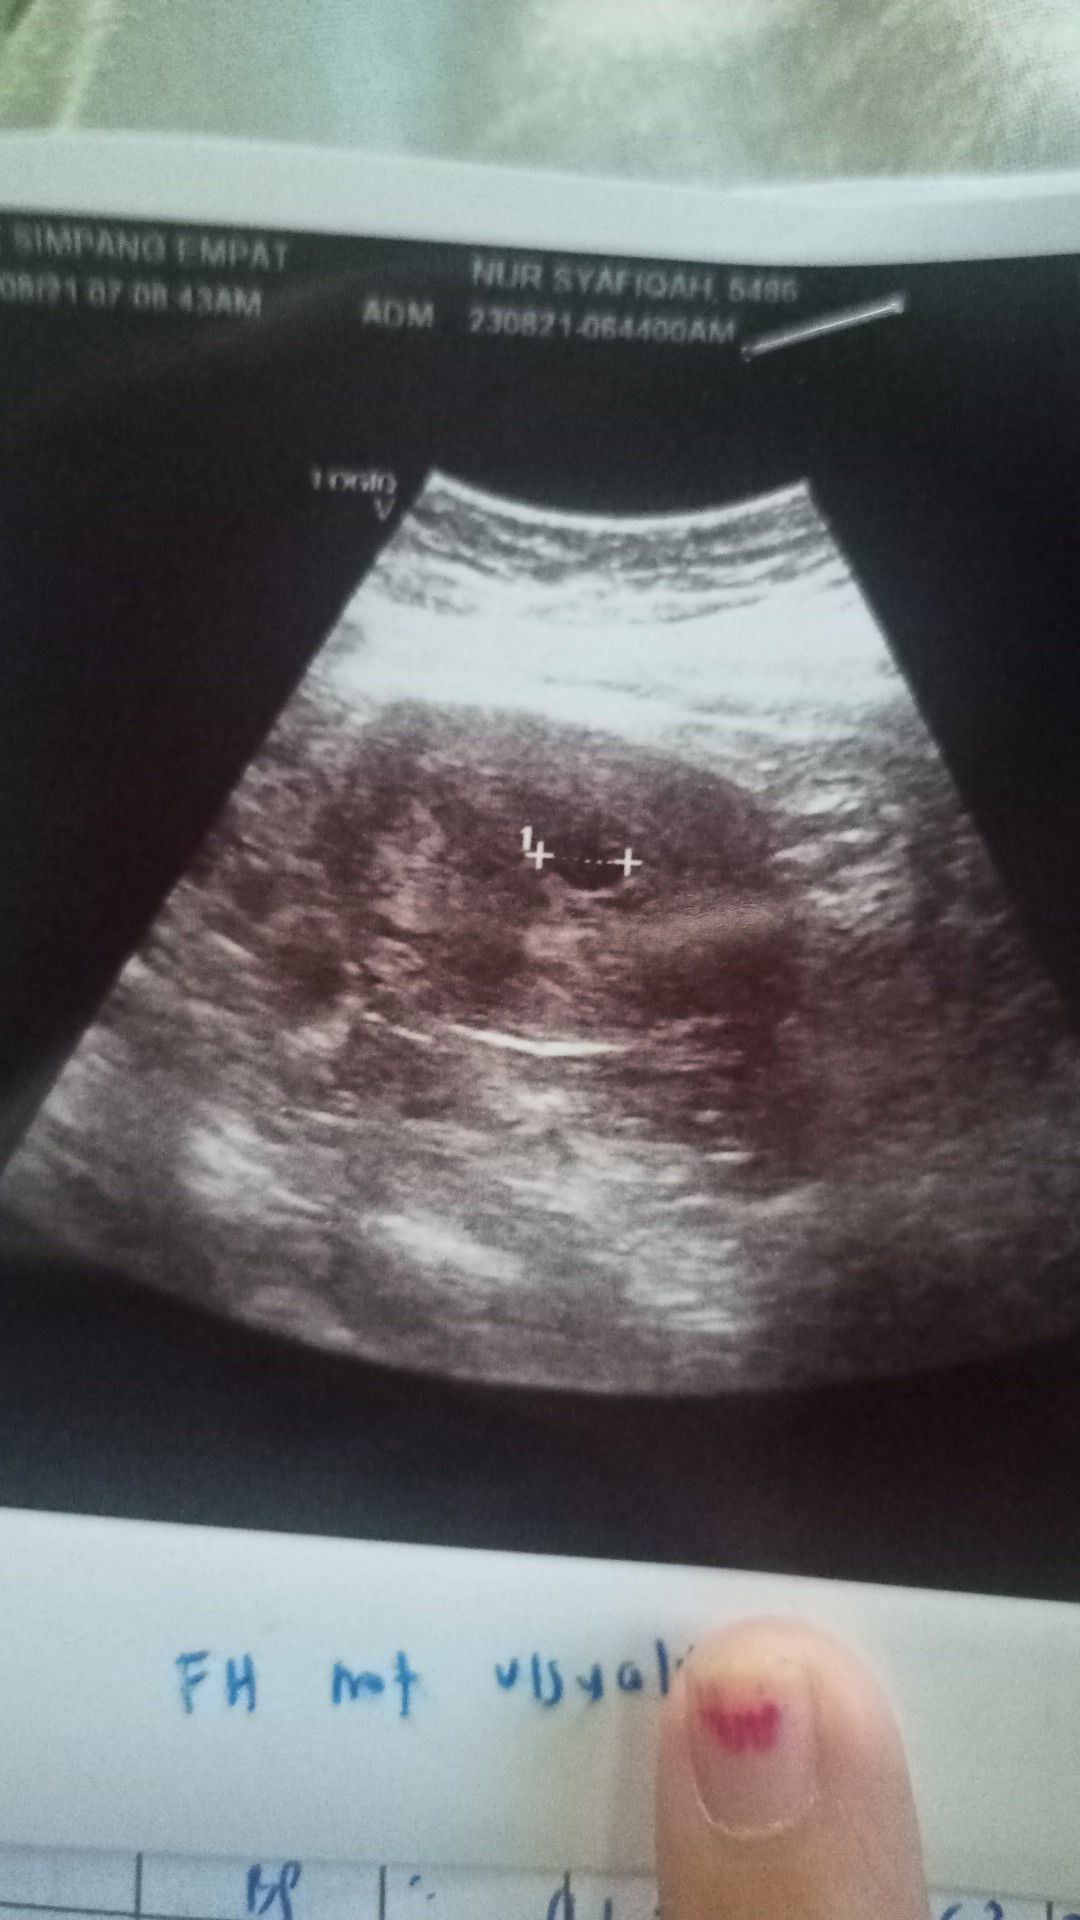

hai kawan²..sy nak tanya...sy lewat dtg bulan baru 5 hari untuk bulan ini...tp 21/1 nie sy ad keluar darah warna coklat tp sikit sangat².....keesokan nya smpai ari ini tiadaa darah lg keluar...sy bingung sekejap..tak tau itu darah apaa...xkan laaa sy period tp seari tu je..n sikit sangat²..sekarang sy mengalami mual² pening..perut sentiasa rasa sebu..sy bru keguguran anak kedua pada bulan 9 tahun 2021..#ingintahu #bantusharing #pleasehelp #seriusnanya